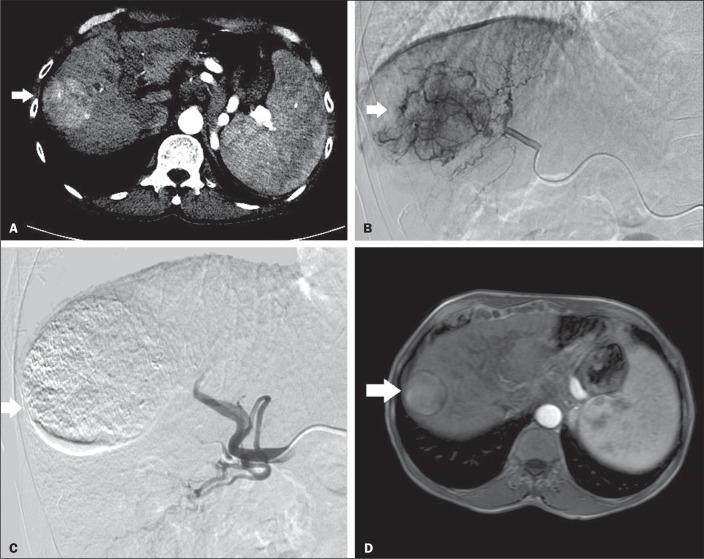

To evaluate the degree of tumor necrosis after transarterial chemoembolization (TACE), used as a bridging therapy in patients awaiting liver transplantation, and its effect on survival.

This was a retrospective cohort study involving 118 patients submitted to TACE prior to liver transplantation, after which the degree of tumor necrosis in the explant and post-transplant survival were evaluated.

Total necrosis of the neoplastic nodule in the explant was observed in 76 patients (64.4%). Of the patients with total necrosis in the explanted liver, 77.8% had presented a complete response on imaging examinations. Drug-eluting bead TACE (DEB-TACE), despite showing a lower rate of complications than conventional TACE, provided a lower degree of total necrosis, although there was no statistical difference between the two. By the end of the study period, 26 of the patients had died. Survival was longer among the patients with total necrosis than among those with partial or no necrosis (HR = 2.24 [95% CI: 0.91-5.53]; = 0.078).

In patients undergoing TACE as a bridging therapy, total tumor necrosis appears to be associated with improved patient survival.